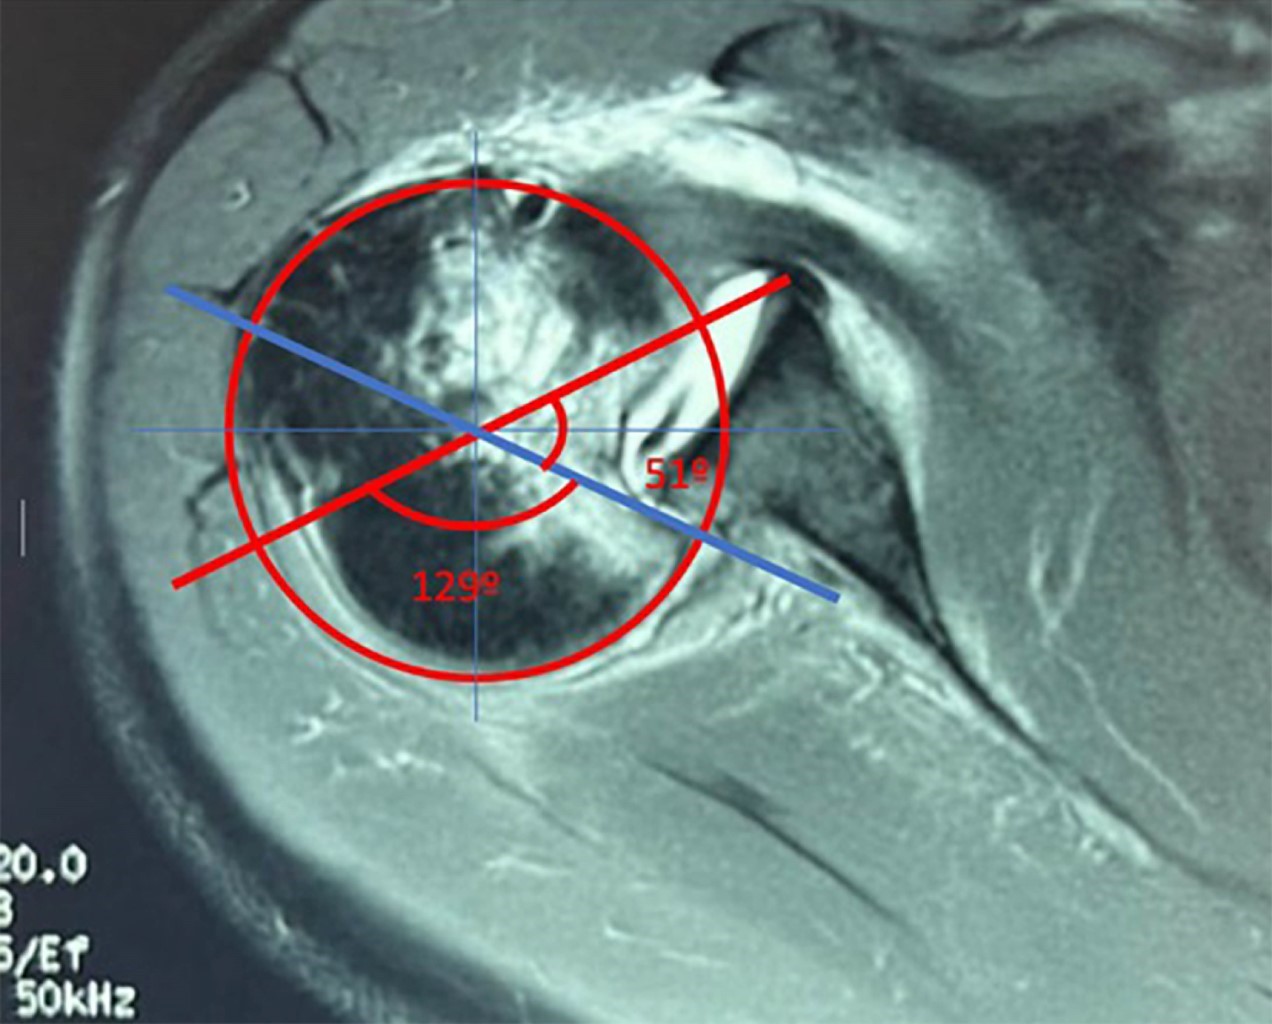

En consulta (ocho semanas desde el accidente), se apreció al paciente con dolor intenso en el hombro derecho (EVA 7/10). A la exploración física del hombro derecho, se observaron arcos de movilidad limitados: flexión 60°, abducción 40°, extensión 15°, aducción 10°, rotación externa 5°. Se solicitó resonancia magnética (RM) simple de hombro derecho, la cual evidenció luxación posterior enganchante de hombro derecho, Hill-Sachs reverso y lesión de subescapular ISAKOS anterior II. Tras la confirmación del diagnóstico, se documentó una fractura por impresión de la cabeza que involucraba el 28.3% de la circunferencia cartilaginosa, sin fracturas relevantes del borde glenoideo posterior. El tamaño del defecto de la cabeza humeral se midió en la RM en un corte axial, justo por debajo de la coracoides. Se colocó un círculo sobre la cabeza humeral y se trazaron líneas que definieron ángulos clave para medir el porcentaje de la superficie articular afectada, con el porcentaje del ángulo del cartílago representando el 100% de la superficie articular y el ángulo del defecto indicando el tamaño estimado del defecto de la cabeza humeral (Figura 1). A las nueve semanas después de la lesión, se realizó tratamiento quirúrgico con reducción abierta y transferencia de subescapular mediante técnica McLaughlin modificada.

La RM y la TC, además de ayudarnos en el diagnóstico, son de gran utilidad para ayudar al cirujano a analizar la localización y evaluar el porcentaje de pérdida ósea, tanto en la cabeza humeral como en la glena. La RM o la TC son necesarias para evaluar dicho porcentaje, lesiones asociadas y orientar al cirujano hacia la mejor opción de tratamiento.11 Gerber y colaboradores proponen un método para la medición del defecto óseo en RM o TC; en la RM se mide en un corte axial a nivel de la apófisis coracoides o inmediatamente por debajo de la misma, se coloca un círculo sobre la cabeza humeral, se traza una línea desde el centro del círculo hasta el cartílago inmediatamente adyacente a la tuberosidad menor y otra línea desde el centro del círculo hasta el extremo posterior del cartílago adyacente a la inserción del infraespinoso, esta área es el ángulo de superficie articular. Un segundo ángulo, el ángulo del defecto, es el ángulo formado por las líneas que conectan, primero, el límite anterior y, segundo, el límite posterior del defecto con el centro de la cabeza humeral. El porcentaje del ángulo del cartílago representa el 100% de la superficie articular y el ángulo del defecto es el tamaño estimado del defecto de la cabeza humeral.12

Figura 1